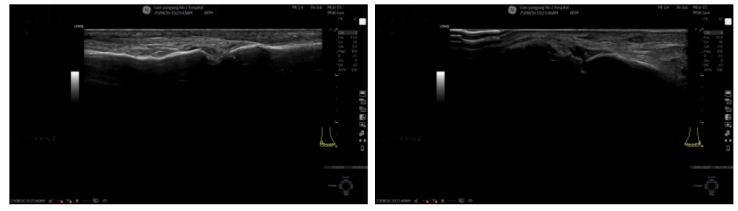

图2. 右侧踝关节浅表超声2024-03-13 第一跖趾关节浅表超声:侧第一跖趾关节滑膜增厚伴痛风结晶形成;双侧第一跖趾关节内侧云雾状强回声(痛风石?);右侧第一跖趾关节积液;双侧第一跖趾关节可见骨侵蚀(图3)。

图3. 第一跖趾关节浅表超声2024-04-18 左侧腕关节浅表超声:左侧腕关节滑膜增厚伴痛风石形成;左侧腕关节少量积液(图4)。